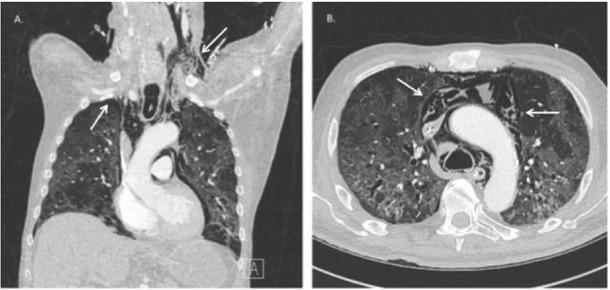

In the absence of respiratory improvement, imaging was performed 2 days later. Chest radiography showed a right-sided apical pneumothorax, which was not yet present on X-ray 3 days prior. Subsequently, a chest CT scan was performed, as shown in Figure 2, confirming the presence of a right-sided ventral pneumothorax, subcutaneous emphysema up to the left side of the neck and an extensive pneumomediastinum. No airway injury was identified on CT; therefore barotrauma was considered to be the most likely cause. Conservative treatment with addition of antibiotics was chosen. The patient’s respiratory status gradually improved. He received a tracheostomy and was successfully weaned off the ventilator.

Figure 2

Chest CT showing (A) a right-sided apical pneumothorax and subcutaneous emphysema up to the left side of the neck and (B) extensive pneumomediastinum